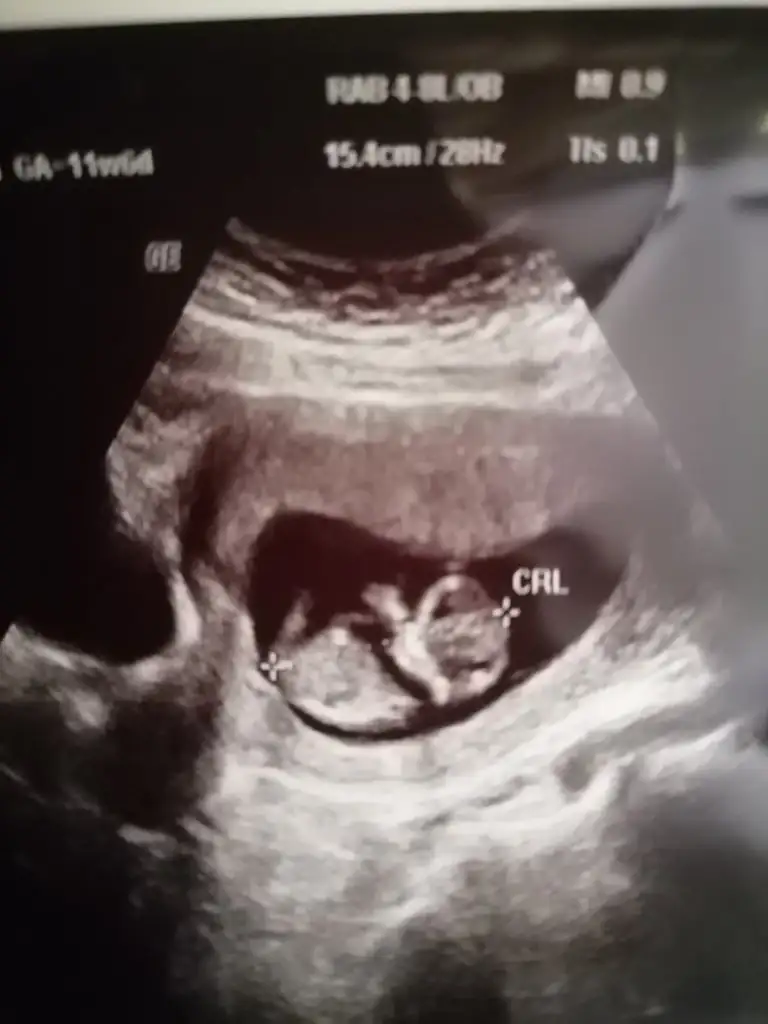

Merhaba canım benim ultrason görüntüsünü de yorumlar mısın Sence kız mı erkek miNub teorisine göre kız gibi

Maalesef Görüntüler net değil nub için yandan görüntü lazımMerhaba canım benim ultrason görüntüsünü de yorumlar mısın Sence kız mı erkek mi Eki Görüntüle 2896592